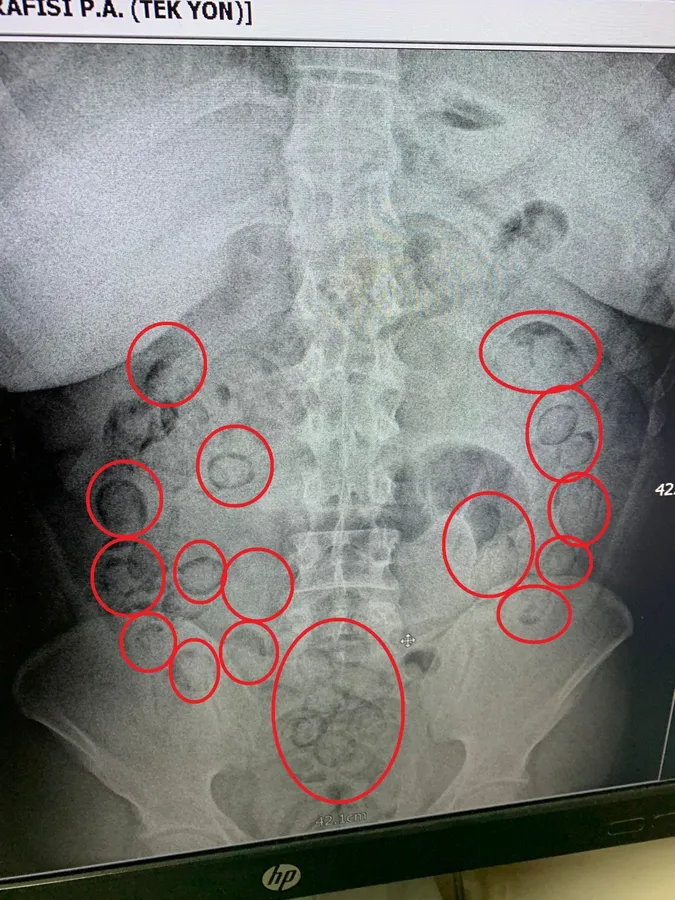

15 Ekim 2025 tarihinde Narkotik Suçlarla Mücadele Şube Müdürlüğümüzce yapılan analizler sonucu ekiplerimizce şehirlerarası yolda yapılan şok uygulamada gözaltına alınan yabancı uyruklu A.M. (20)’nin şüpheli hareketleri olduğu tespit edilmiş, Aksaray Eğitim Araştırma Hastanesinde yapılan iç beden muayenesinde mide içerisinde toplam (101) parça halinde (433) gram metamfetamin maddesi ele geçirilmiştir.